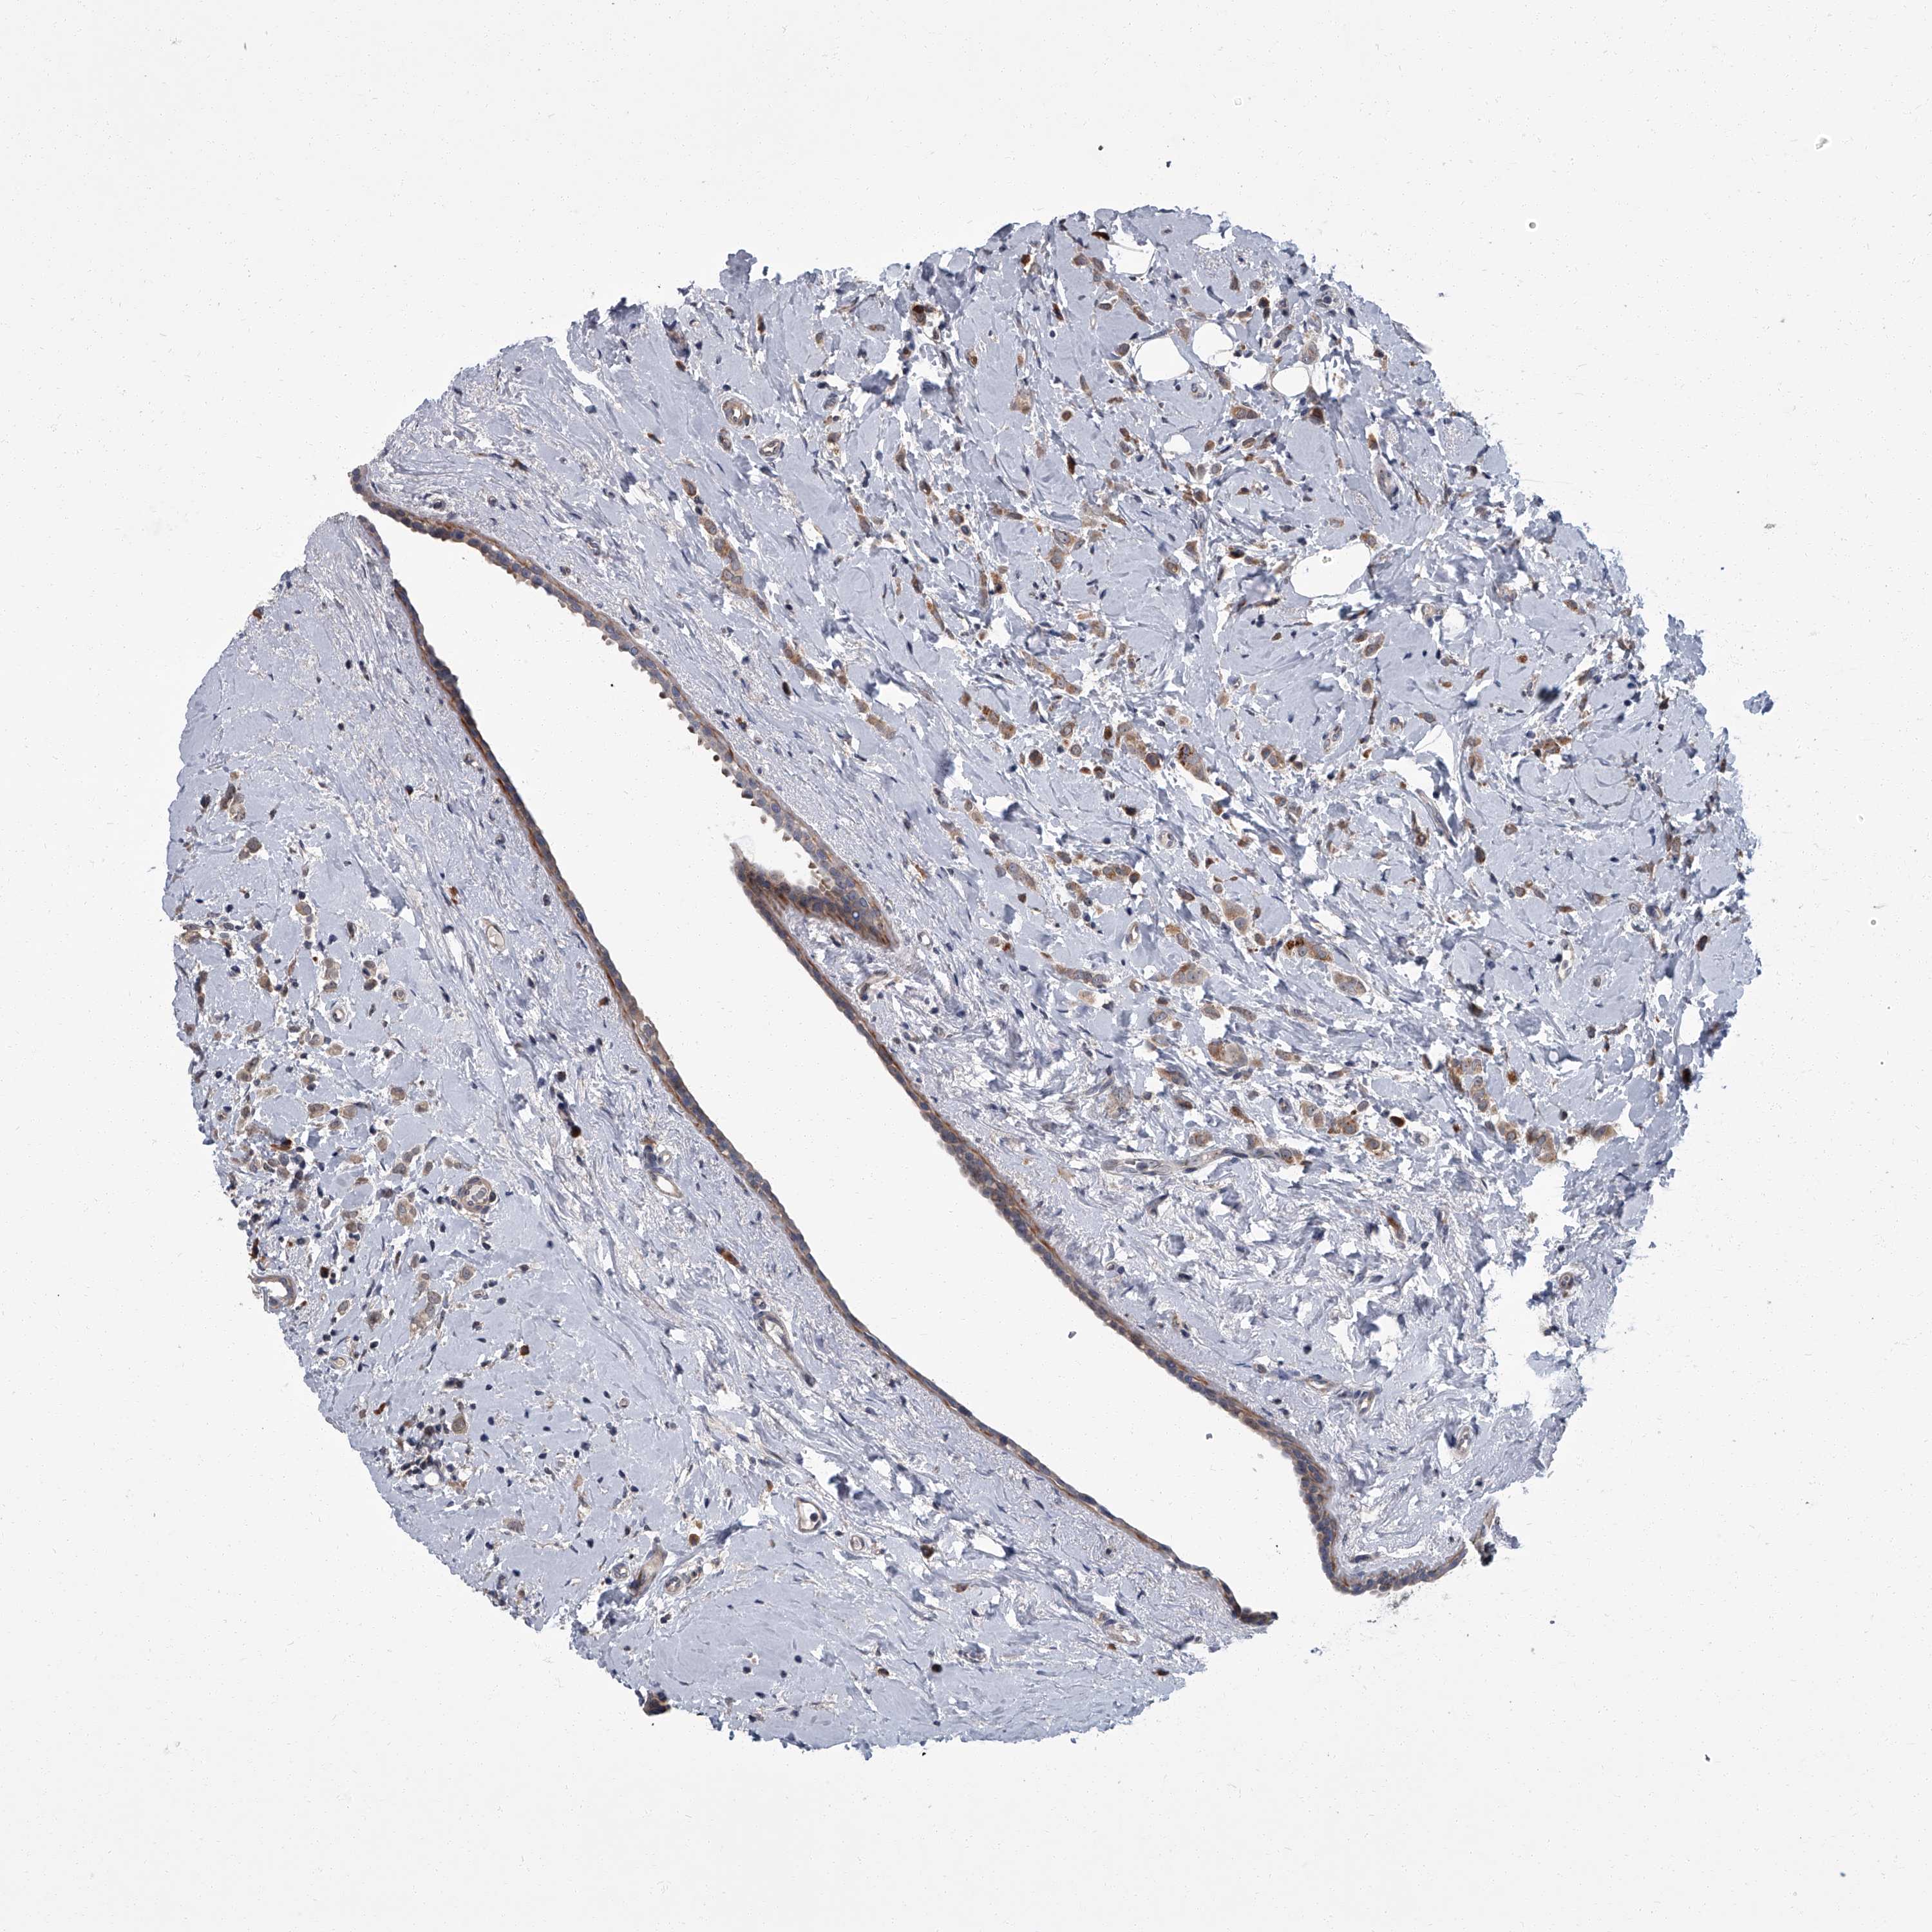

BRCA TCGA BRCA VALIDATION PROTEIN EXPRESSION

Breast cancer

Human cancer